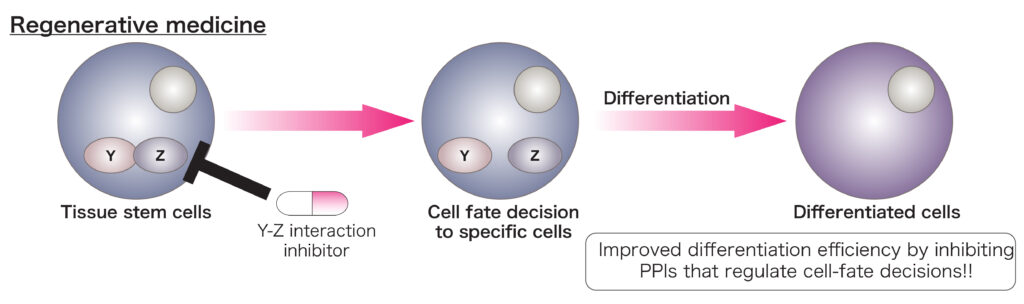

Protein-protein interactions (PPIs) have been demonstrated to regulate cell-fate decisions and tumor malignancy. In previous studies, Dr. Yamada worked on regenerative medicine and disease-modeling using human pluripotent stem cells (hPSCs) and the functional roles of PPIs in sarcoma.

B. Regulatory roles of PPIs in cell-fate decision

The methods that differentiate stem cells to desired cells with high efficiency have not been completely established. Identification and targeting of PPIs that are responsible for cell-fate decision would improve the current differentiation protocols